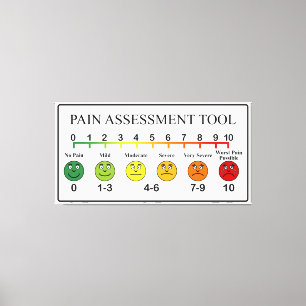

Medical Pain Assessment Tool Chart

PriceCA$276.00

Medical Pain Assessment Tool Chart Canvas Print

PriceCA$428.00